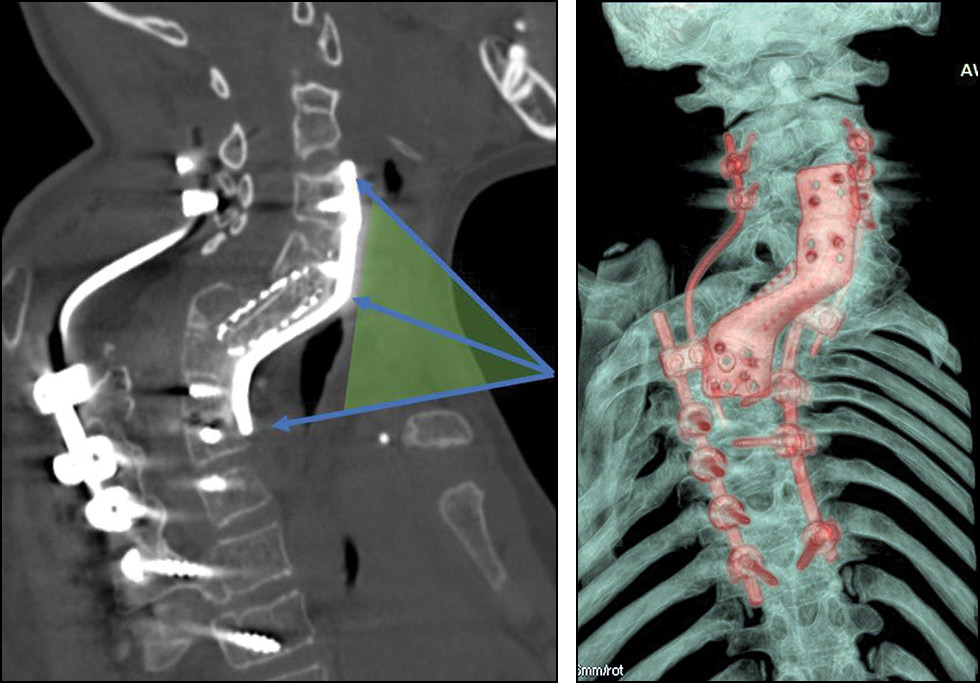

Пациенту выполнены диагностические исследования: компьютерная томография (КТ), магнитно-резонансная томография (МРТ) и рентгенограмма шейно-грудного отдела позвоночника (в прямой и боковой проекции) (рис. 1).

Рис. 1. Компьютерная томография (a), магнитно-резонансная томография (b) и рентгенограмма (c) шейно-грудного отдела позвоночника. По данным КТ и МРТ выявлен стеноз позвоночного канала С4–Тh4 с МР-признаками миелопатии. По данным КТ и рентгенографии позвоночника картина врождённой аномалии позвоночника следующая: заднебоковой клиновидный добавочный полупозвонок С7, локальный угловой кифоз на уровне С6–7 позвонка с наличием костного блока тел и задних элементов Th1–3 позвонков и заднебоковым клиновидным полупозвонком Th4–Th5.

Fig. 1. Computed tomography (a), magnetic resonance imaging (b) and radiograph (c) of the cervicothoracic spine. CT and MRI data revealed stenosis of the C4–Th4 spinal canal with MR signs of myelopathy. According to CT and radiography of the spine, the picture of the congenital anomaly of the spine is as follows: posterolateral wedge-shaped accessory hemivertebra C7, local angular kyphosis at the level of the C6–7 vertebra with the presence of a bone block of the bodies and posterior elements of the Th1–3 vertebrae and a posterolateral wedge-shaped hemivertebra Th4–Th5.

На основании клинико-лучевых методов обследования (см. рис. 1) установлен диагноз: аномалия развития шейно-грудного отдела позвоночника. Врождённый кифосколиоз шейно-грудного отдела позвоночника IV степени. Стеноз позвоночного канала с передней компрессией спинного мозга на уровне С7–Тh1. Грудная миелопатия. Верхний смешанный дистальный парапарез, нижний спастический парапарез. Нарушение функции тазовых органов (группа С по Frankel, Ashworth 3, ASIA — движение 82, тактильная 86, болевая 84).